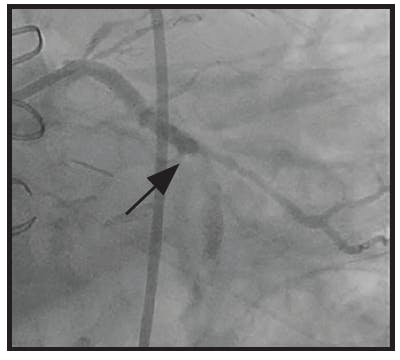

A 65-year-old man presented emergently with an inferior wall MI. The initial angiogram confirmed a distal occlusion of the RCA with TIMI 0 flow and extensive clot burden (Figure 1).

INTERVENTION

Initial angiography revealed an occlusion of the distal RCA. Mechanical coronary aspiration was performed frontline with CAT RX and Penumbra ENGINE to remove the high thrombus burden. After one pass with CAT RX, the high thrombus burden was removed, resulting in TIMI 3 flow.